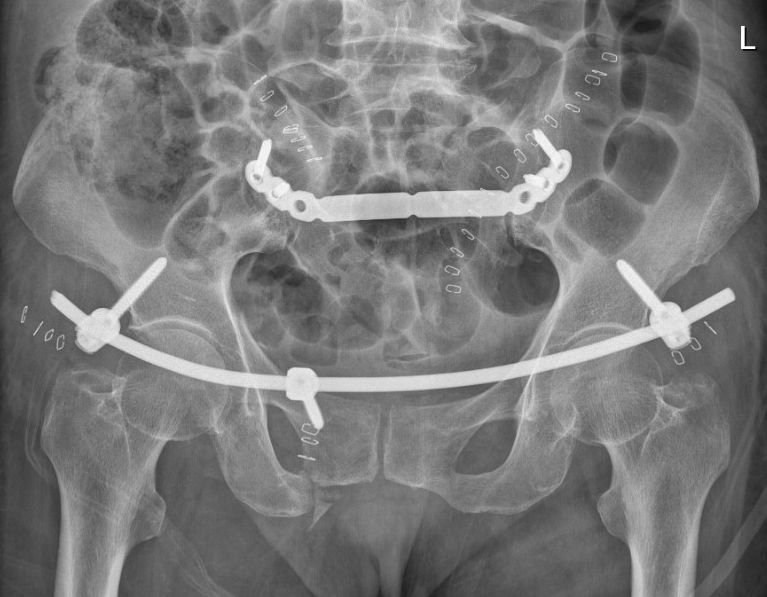

创伤骨科二病区应用infix 门型钢板微创治疗骨盆c型骨折手术成功实施

曾都医院成功开展骨盆骨折infix 固定 骶髂关节螺钉内固定手术

【智慧骨科】机器人联合infix,fns新型内固定技术微创固定环骨盆骨折

78岁老太骑车摔倒骨盆多发骨折,骨科机器人联手infix内固定微创手术

85岁阿婆不慎骨盆骨折infix微创手术解难题术中出血仅10毫升